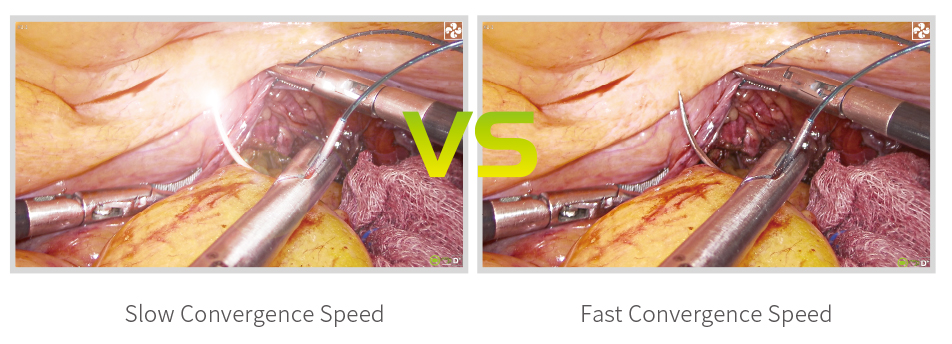

Adaptive Light Source Adjustment

There is no need to frequently adjust the light intensity, and the light source convergence speed is less than 100ms to adapt to all surgeons.